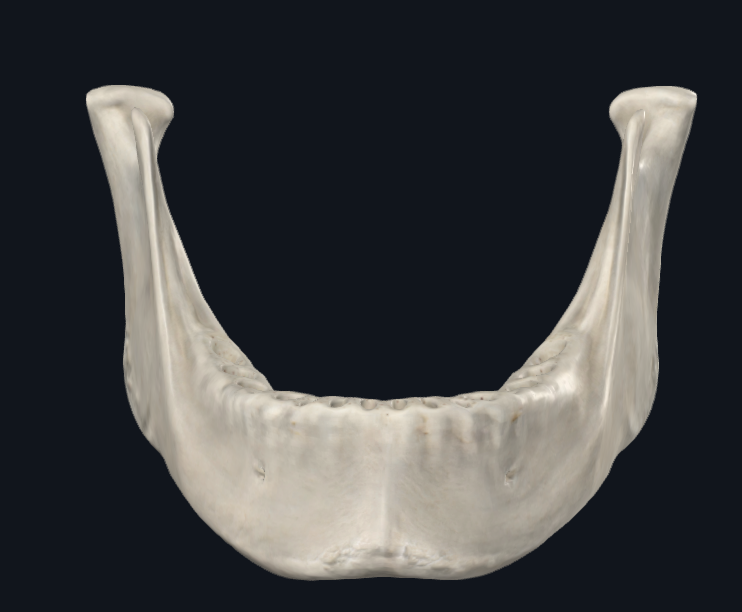

Mandíbula

Cuerpo Mandibular

Ramas mandibulares